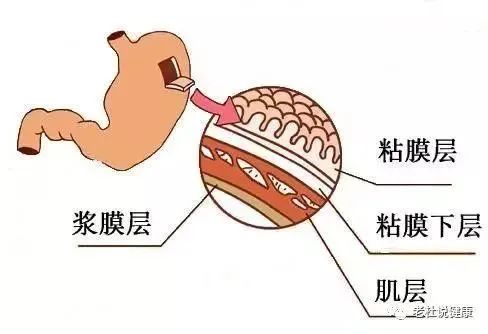

2019年,阿英腹部间断疼痛被诊断为“胃癌”,在中大五院胃肠外科行胃癌根治术,但术中医生意外发现其肝脏有微小转移灶,随即联合肝胆外科行肝脏转移瘤切除术,术后一个月检查发现,肝脏再次出现多发转移瘤。

肿瘤中心副主任曾林涓主任医师介绍,“根据病理特征,该患者的肿瘤组织免疫组化染色HER-2(+++),这意味着,她适合曲妥珠单抗靶向治疗联合化疗。在多学科讨论,全面评估患者病情后,我们制订了个体化的精准治疗方案。”